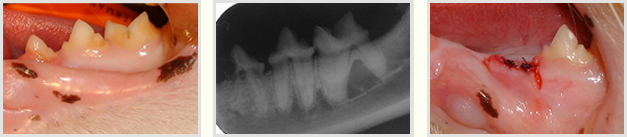

Kronenamputation ohne Wurzelextraktion nach Dentalröntgen:

Bei einer im Dental-Röntgen erkennbaren Wurzelpathologie vom Typ 2 kann bei TR (FORL) eine neue Form der Therapie angewendet werden:

"die Kronenamputation mit intendierter Wurzelretention".

Dabei wird nach Präparation eines Gingivalappens die Krone mit einem Bohrer in der Turbine abgetrennt und der Gingivalappen über der Wunde verschlossen. Vor der Naht des Gingivalappens wird zur Kontrolle des richtigen Absetzens des Zahnes ein Röntgen angefertigt, das auch als Vergleichsröntgen für das Kontrollröntgen nach etwa 6 bis 12 Monaten dient. Mit dem Kontrollröntgen wird der vollständige Umbau der Wurzel-Dentin-Struktur im Knochen kontrolliert, Granulome, Abszesshöhlen oder andere Entzündungsvorgänge werden ausgeschlossen. Der Vorteil dieser Methode liegt darin, dass die oft schwierige Extraktion von Katzenzähnen, vor allem jener mit Wurzeln vom Typ 2, umgangen werden kann. Zudem ist die Therapie mit Dentalröntgen rascher durchzuführen.

Zahnröntgen unverzichtbare Voraussetzung

Ein Zahnröntgen ist absolute Voraussetzung für diese Therapie, da kein Zusammenhang zwischen Gingival- oder Parodontalerkrankung und Wurzelresorption besteht, im Gegenteil:

Bei einer schweren Parodontalerkrankung kommt es seltener zu Ab- und Umbau der Zahnwurzeln von mit FORL befallenen Zähnen. Bei chronischer Mundhöhlenentzündung (Gingivitis-Stomatitis oder "Plasmazellgingivitis") und bei schwerer Parodontitis ist diese Methode nicht indiziert, da hier meist Wurzeln vom Typ 1 vorliegen und diese vollständig entfernt werden müssen.